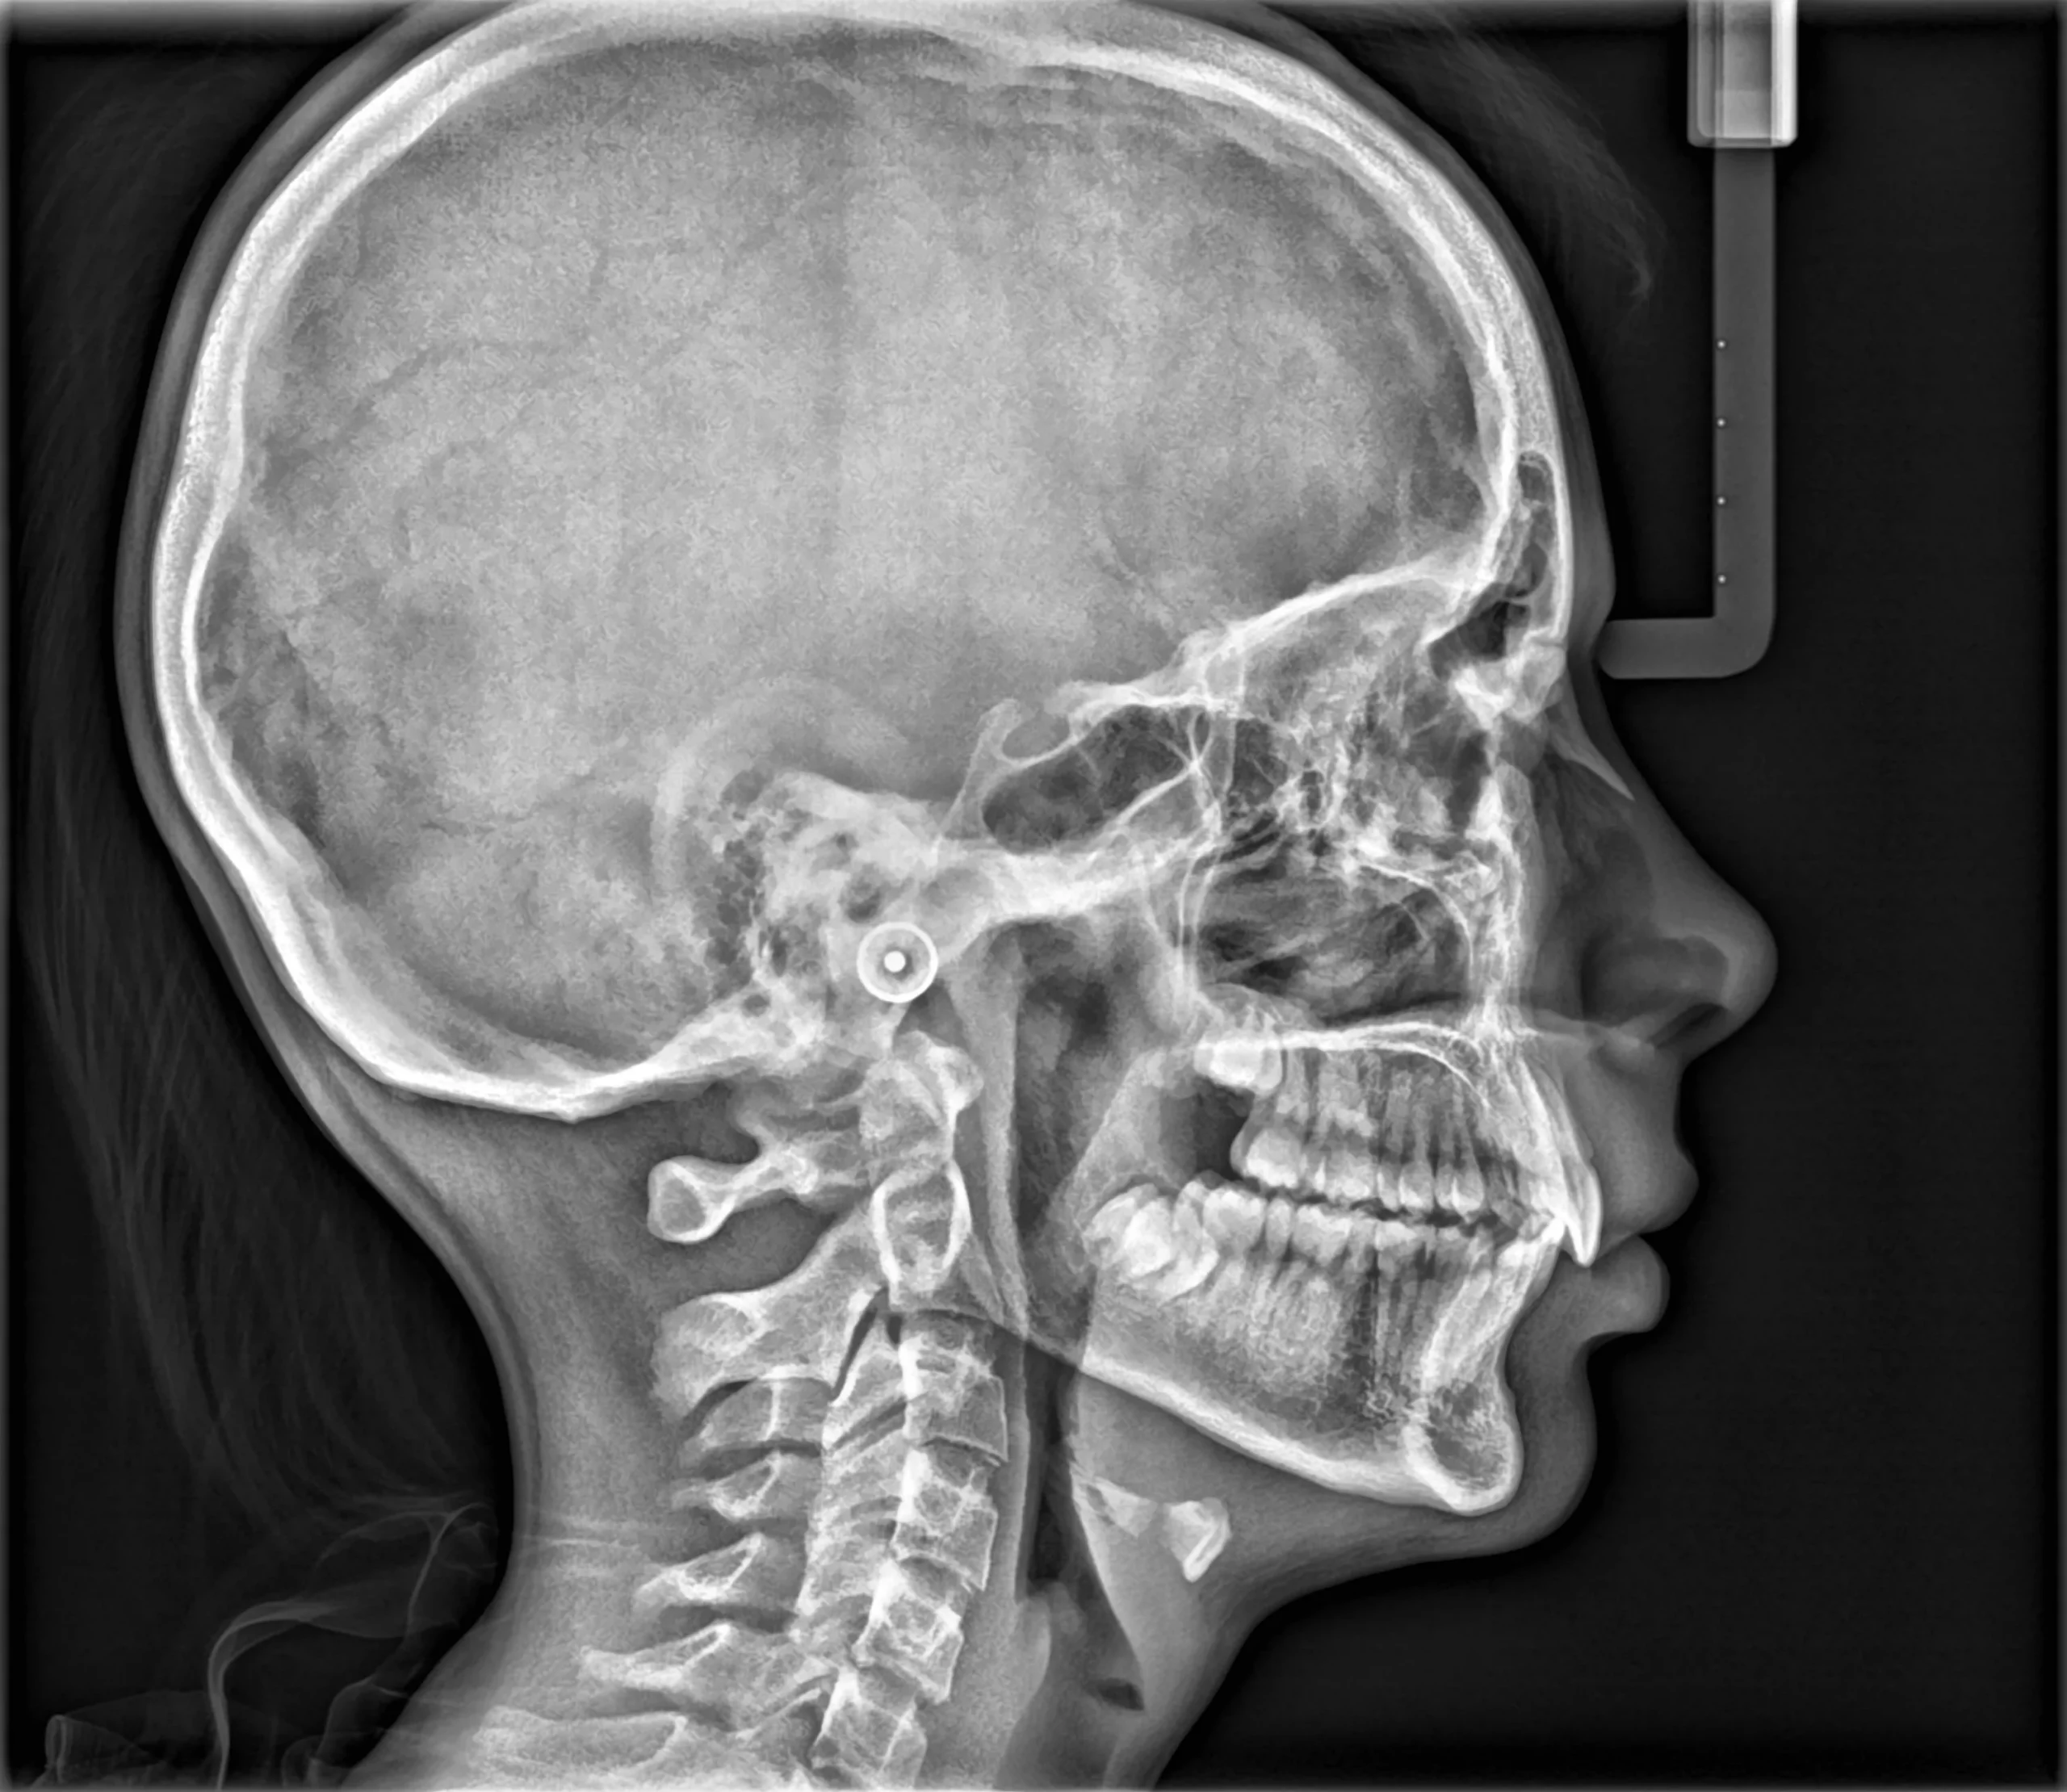

S novim Scan Ceph modulom i drugim inovacijama, najinteligentniji CBCT sustav na svijetu sada je još pametniji i svestraniji nego ikad. Sustav redefinira kvalitetu i upotrebljivost, što ga čini savršenim sustavom snimanja za stomatologe i specijaliste koji žele novu razinu preciznosti.

Pametne inovacije potiču preciznost na svakom pregledu

Kristalno jasne slike s ograničenim artefaktima i šumom